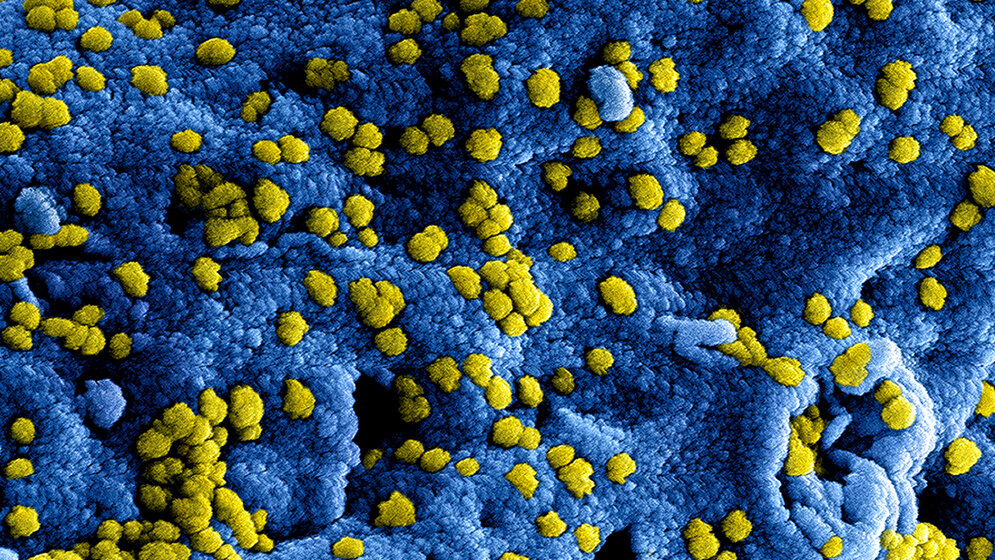

Laut Wellcome Trust werden die COVID-19-Kosten etwa 11 Billionen USD bis Ende 2021 betragen. Das Nicht-vorbereitet-sein kostet deutlich mehr als die Eindämmung von Infektionskrankheiten. Viele Ausbrüche schaffen es noch nicht einmal in die Nachrichtensendungen. Anbei finden Sie die „Top 10“ der vergangenen Jahre. Quelle: WHO/IHM data as of 12 January 2018